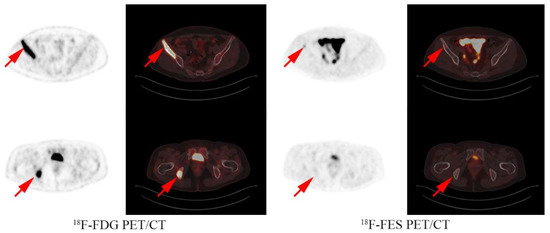

Figure 4.

Analysis examples: A 53 year old female had both FES positive and negative lesions in the bone and received capecitabine treatment with a PFS of 15 months.